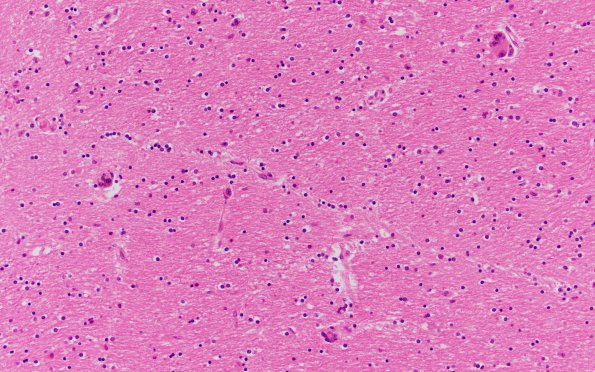

6B3 HIVE & HIVL (Case 6) H&E N2 11

The histopathology in this case consists of astrocytosis and scattered multinucleate giant cells (H&E).